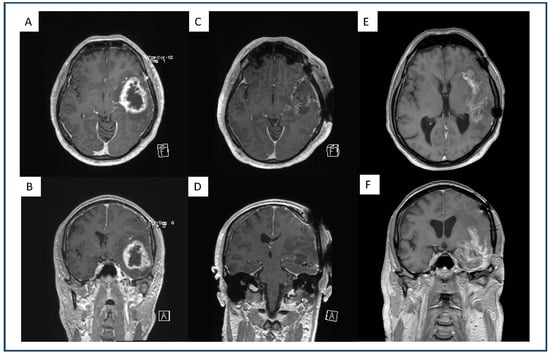

4.1. Multifocal and Midline-Crossing Relapse

4.2. Sharp Demarcated Lesions

4.3. Analysis of Intratumoral Hemorrhage